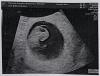

Кто-то делал УЗИ на сроке 9-10 недель? Что там видно? Пришлите пожалуйста фото с УЗИ, если есть

Было видно как пальчиками перебирал) и ручки, ножки , голова , плавал, шевелился)

Фотки нет , но уже прям маленький человек в 10 недель. Ручки ножки , голова )))

Сегодня ходила 10,6 ножками ручками дергает во всю))